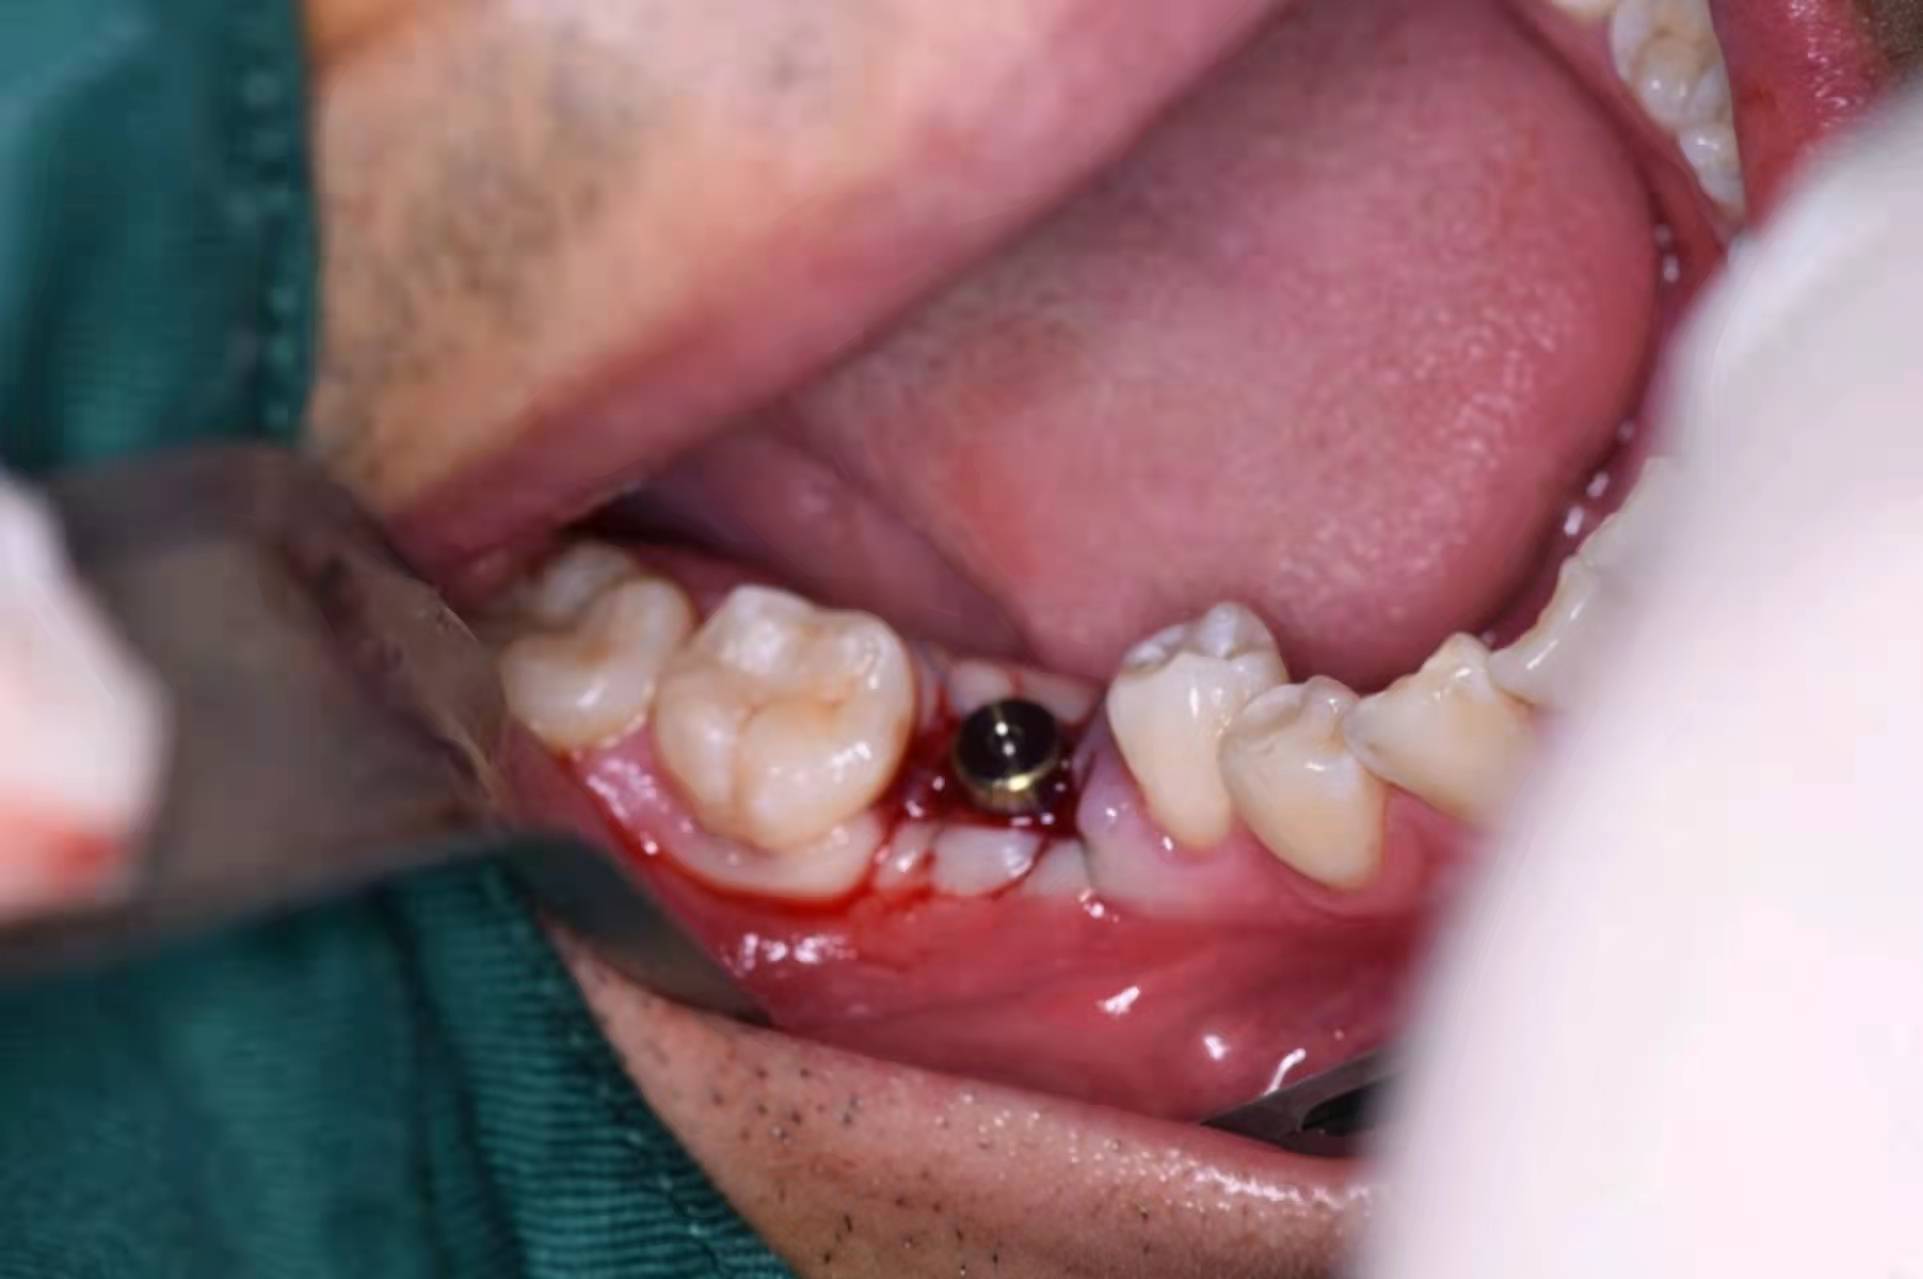

擰入愈合基臺:

在種植導(dǎo)板引導(dǎo)下植入,位置更加準(zhǔn)確,將種植的位置軟組織環(huán)切,然后植入種植體,術(shù)后愈合基臺封閉。這種方式,術(shù)后不用縫合,不用再拆線,患者的舒適度較高。